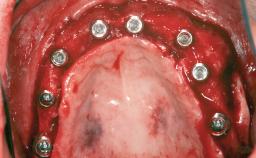

# of Teeth 6

# of Implants 4

Type of Implants One-Piece|Reduced-Diameter